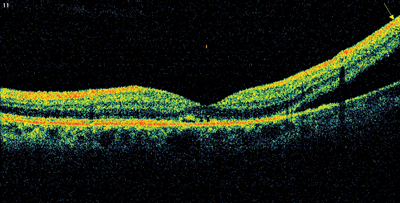

Examination of the right eye showed yellow retinal lesions, thought to signify drusen. OCT scanning of the left macula demonstrated subretinal and intraretinal fluid (Figure 1a). Fundus fluorescein angiography (FFA) is not routinely performed in our unit for diagnosis of AMD, but is reserved for cases that don’t respond to treatment or present a diagnostic challenge. FFA was not done for this patient as part of her initial work-up either. The patient was referred to the one-stop macula clinic, where she was diagnosed as wet AMD and initiated on a course of three intravitreal ranibizumab (0.5mg) injections, administered four weeks apart. Visual acuity improved to 6/6. OCT showed recovery of normal foveal appearance (Figure 1b), though peripheral tenting was still present.

Figure 1b: OCT image of the left macula following the course of intravitreal ranibizumab injections.

Macula contour is normal but peripheral tenting is still visible.